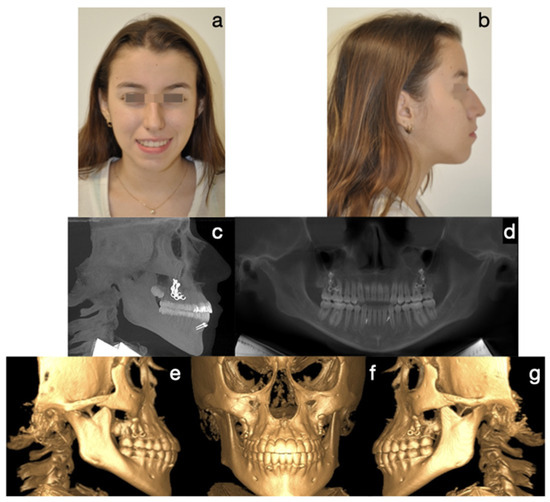

The contributions within this edition will explore various aspects of diagnostic modalities, including advanced radiology techniques such as cone beam computed tomography (CBCT) and magnetic resonance imaging (MRI), which offer detailed anatomical information for precise diagnosis and treatment planning. Additionally, the articles included will discuss the application of optical imaging and diagnostic tools, providing insights into non-invasive methods for detecting early signs of disease and monitoring treatment responses.